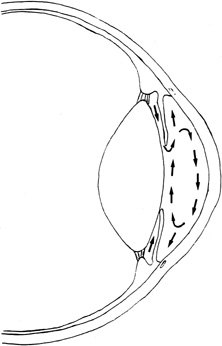

The aqueous humor is a transparent, colorless solution continuously formed from plasma by the epithelial cells of the ciliary processes. It is secreted into the posterior chamber, passes from the posterior chamber through the pupil into the anterior chamber, and is drained at the anterior chamber angle. Most of the aqueous drains into the venous circulation via the trabecular meshwork, Schlemm's canal, scleral collector channels, and aqueous and episcleral veins; the remainder drains into the orbit via the interstices of the ciliary muscle, the suprachoroidal space, and the sclera (Fig. 1). The composition and formation of aqueous resembles that of cerebrospinal fluid.1 Aqueous humor is thought to serve several functions:

Fig. 1. Cross section through the anterior segment of the eye illustrating the chamber angle. Aqueous humor is formed by active secretion from the ciliary processes (A). Drainage occurs via the outflow pathways, principally the trabecular meshwork (B) and Schlemm's canal (C) into the aqueous veins (D). A smaller proportion of the aqueous humor makes its way directly into the ciliary body (uveoscleral pathway) and is drained by way of the ciliary muscle, the suprachoroidal space, and the sclera (E). (From Karnezis TA, Murphy MB: Dopamine receptors and intraocular pressure. Trends Pharmacol Sci 9:389–390, 1988, with permission.)